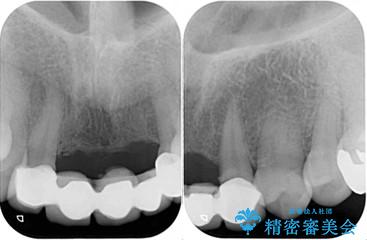

- アンバランスな色や形、歯肉ラインの黒い縁が目立ってしまったブリッジの作り直しを希望して来院された患者様です。

自然な仕上がりとするため、金属を使用しないオールセラミックブリッジにより補綴治療を行うこととしました。